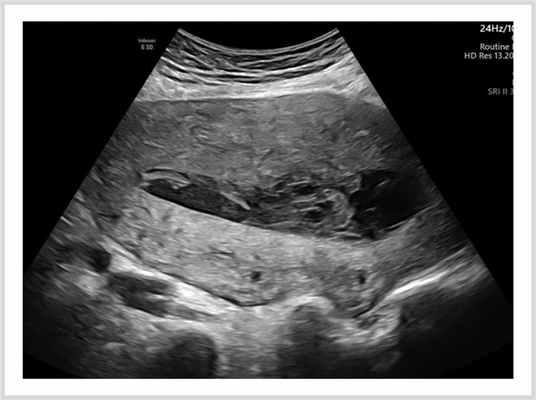

Расширение полости матки более 10 мм с неоднородным содержимым и субинволюцию матки без клинических проявлений воспалительного процесса расценивали как гематолохиометру (рис. 2). Рис. 2. УЗ-картина гематолохиометры.